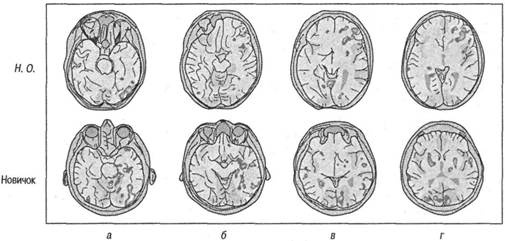

Н. О. и ОМР. В исследовании, проведенном Солсо (Solso, 2001), Н. О. рисовал шесть портретов, лежа на спине в ограниченном пространстве аппарата для ОМР. Эту задачу выполнял также контрольный испытуемый, чтобы обеспечить сравнение мозговой активности Н. О. и новичка. Результаты активности церебрального кровотока Н. О. и новичка показаны на рис. 6.4.

Как и ожидалось, большая активность была зарегистрирована в правом полушарии испытуемых, ответственном за восприятие и обработку геометрических форм. В восприятии лица прежде всего участвует заднетеменная область, как показано на рис. 6.4 в колонке а и до некоторой степени — б, и эксперт и новичок обнаружили значительную активность в этой области. Однако если вы внимательно рассмотрите различия между экспертом и новичком, то увидите, что у новичка отмечается более интенсивный кровоток к правой заднетеменной области (рис. 6.4, а). Почему у эксперта обнаруживается менее интенсивный кровоток при обработке лиц? Ответ может стать одним из ключевых элементов в нашем понимании особенностей памяти экспертов.

Рис. 6.4. ОМР-снимки Н. О. и контрольного испытуемого (нехудожника), отражающие активность в правой теменной области у обоих (см. колонку а). Эта область участвует в восприятии лица, но кажется, что нехудожнику требуется больше энергии для обработки лица, чем Н. О. В колонках в и г отмечается увеличение кровотока в правой лобной области художника, что указывает на абстракцию информации более высокого порядка (Solso, 2000, 2001)